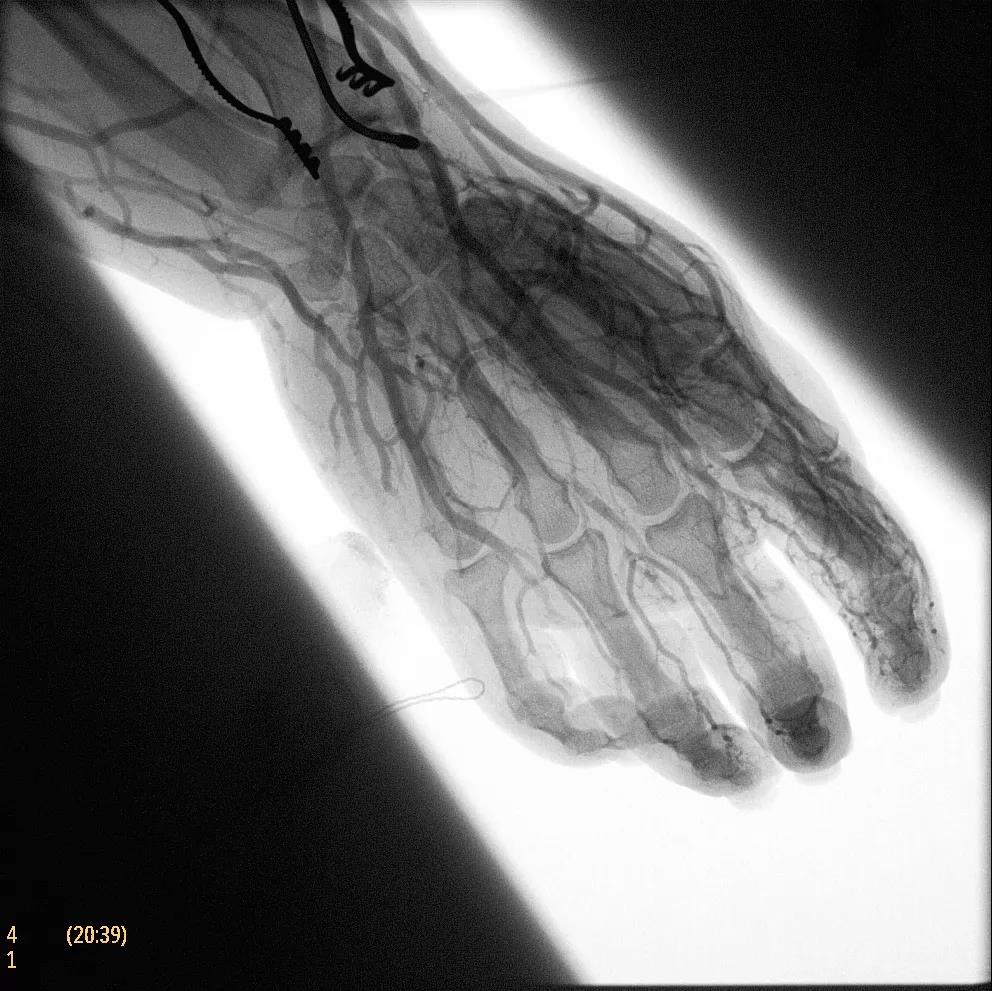

據(jù)器械之家了解到,移動(dòng)式C型臂是X射線系統(tǒng),可帶入手術(shù)室(OR),在整形外科、創(chuàng)傷和血管手術(shù)等各種手術(shù)過程中提供實(shí)時(shí)圖像引導(dǎo)。Zenition70使醫(yī)院能夠最大限度地提高OR性能,增強(qiáng)臨床能力并為員工提供高質(zhì)量的用戶體驗(yàn)。

在快速增長的圖像引導(dǎo)微創(chuàng)手術(shù)領(lǐng)域 ,手術(shù)干預(yù)的范圍和復(fù)雜性在繼續(xù)增加,需要治療的患者數(shù)量也在增加。為了以更低的成本治療更多的患者,醫(yī)院需要具有不同能力的多功能C臂組,以便容易地適應(yīng)不同類型的手術(shù)和不同操作者的需要。Zenition 70易于在手術(shù)室之間移動(dòng),易于在患者周圍定位并且操作直觀。